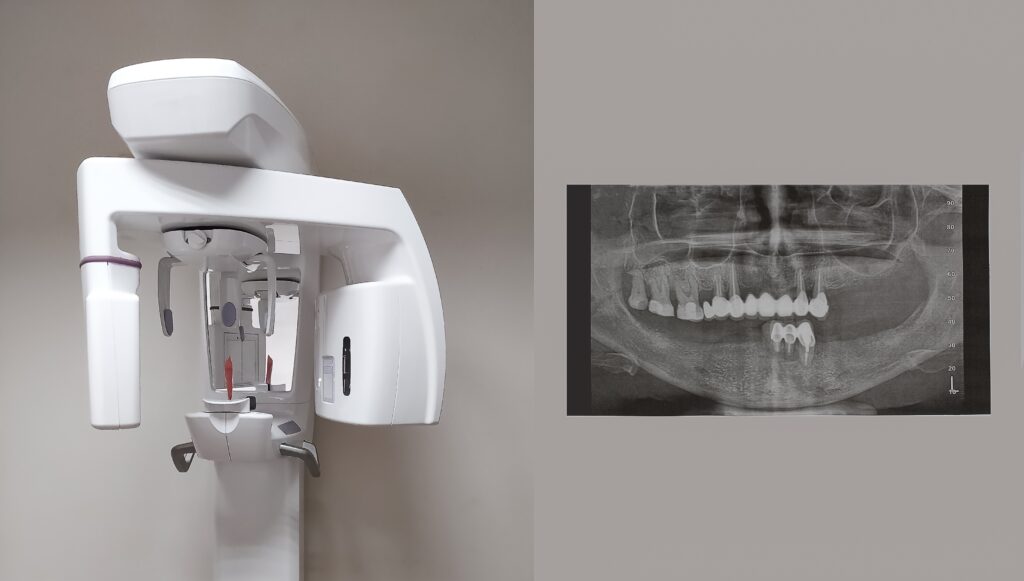

Cone,Beam,Computed,Tomography,Scanner,,No,People

Cone Beam CT Scan

A Cone Beam CT Scan provides a 3D view of your teeth, jawbone, nerves, and sinuses—making it an essential tool for precise diagnosis and treatment planning, especially for implants or extractions. It’s typically recommended before surgical procedures. At Toluca Advanced Dentistry, we offer in-office CBCT imaging forusing advanced, low-radiation technology for your comfort and safety.